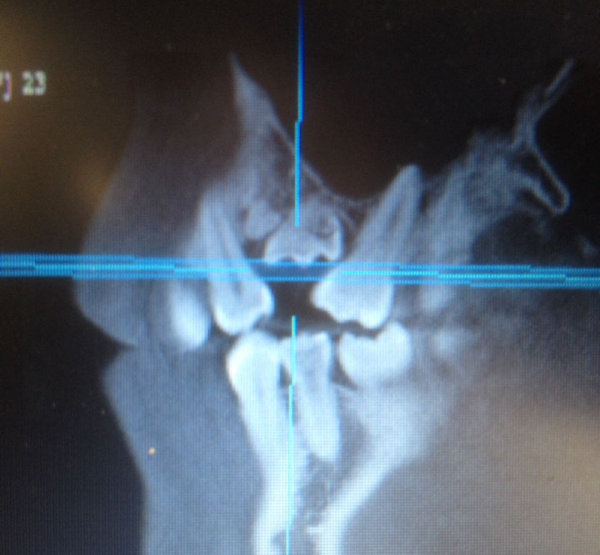

Мне 26 лет, молочные зубы менялись поздно. По личным причинам, когда стал резаться коренной зуб (клык), я не стала вырывать молочный, который был крепким и здоровым. Так на протяжении нескольких лет (очень медленно) прорезался коренной клык и наконец вырос, но на нёбе. Так я ходила с двумя зубками. Никаких неудобств не ощущала. Совсем недавно молочный зуб резко (в течение трёх дней) потемнел.

Что такое Мартини, я не знаю. В вашем случае необходимо обратиться к ортодонту на очную консультацию. После составления плана лечения можно говорить о возможных методах лечения. Молочный зуб однозначно необходимо удалить.